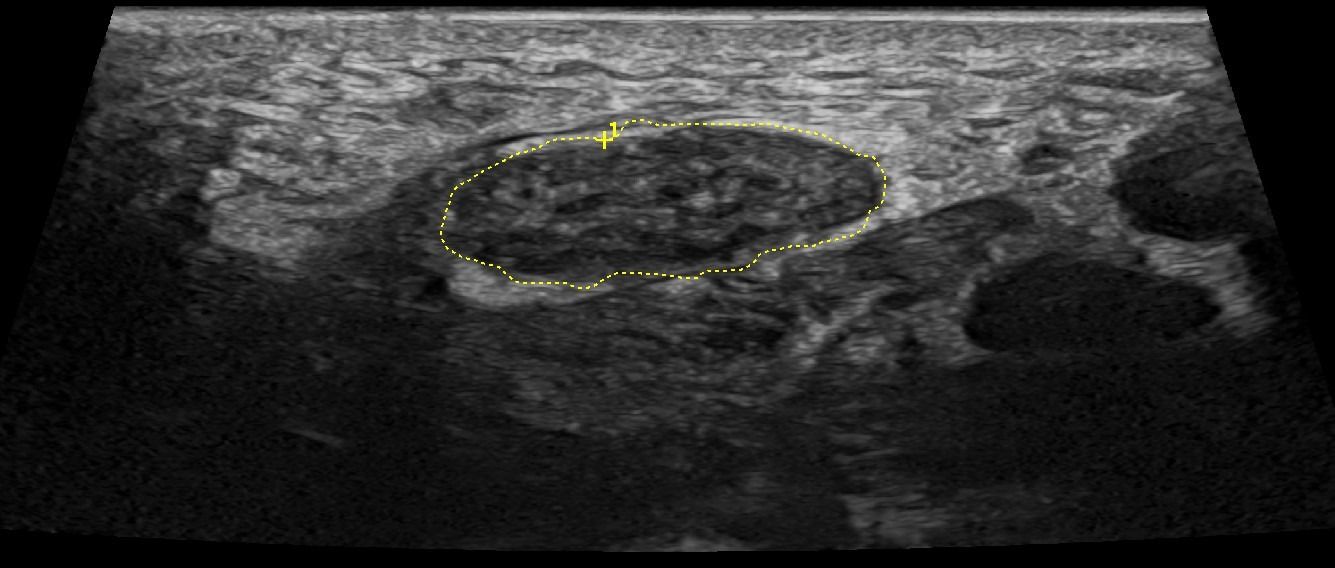

- Focal Lesions (tumors, neuromas)

- Degenerative Changes

- Injuries (trauma, laceration)